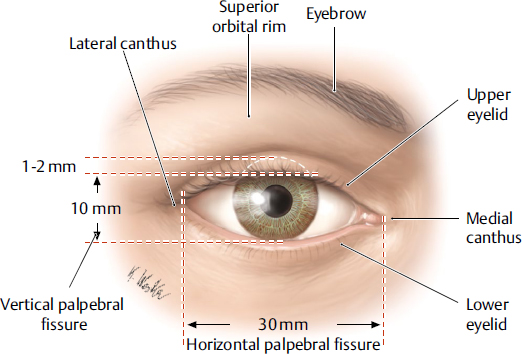

Das Augenlid

Das obere Augenlid hat die wichtige anatomische Funktion einerseits das Auge vor äußeren Einwirkungen zu schützen und andererseits die Hornhaut feuchtzuhalten um eine scharfe Sicht zu gewährleisten (https://plasticsurgerykey.com/browupper-lid-anatomy-aging-and-aesthetic-analysis-2/#:~:text=The%20orbicularis%20muscle%20is%20a,5). Es ist die dünnste Haut des menschlichen Körpers und für gewöhnlich zwischen 5mm und 8mm dick

Das obere Augenlid erstreckt sich nach oben hin(superior) bis zur Augenbraue, die sie von der Stirn separiert. (6)

Das untere Augenlid erstreckt sich nach unten über den unteren Orbitarand hienaus und bildet dort Falten, wo das lose Bindegewebe des Augenlids an das dickere Gewebe der Wange angrenzt.(6) TODO: Bild des Bindegewebes.

522 × 354###

Die Lidspalte hat für gewöhnlich eine Breite (Medialer bis zum Lateralen Canthus) von etwa 28mm bis 30mm (6, das wollen wir aber nochmal recherchieren). Und ist für gewöhnlich zwischen 7mm und 12mm hoch (8mm - 12mm für Frauen) (6, aber das wollen wir nochmal recherchieren, außerdme: von wo bis wo, die Grenzen der Lider??!). Wenn das Auge geöffnet ist, bedeckt das obere Augenlid für gewöhnlich etwa zwischen 1mm bis 2mm der Iris. Die Kante des unteren Augenlids hingegen berührt ganz leicht den Limbus (der etwa 1mm breite Übergangsbereidch zwischen Hornhaut und Lederhaut, quasi die äußere Grenze der Iris).